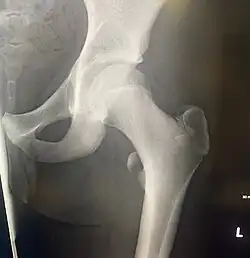

![]() Left hip-joint, opened by removing the floor of the acetabulum from within the pelvis. | |

![]() Upper extremity of right femur viewed from behind and above. | |